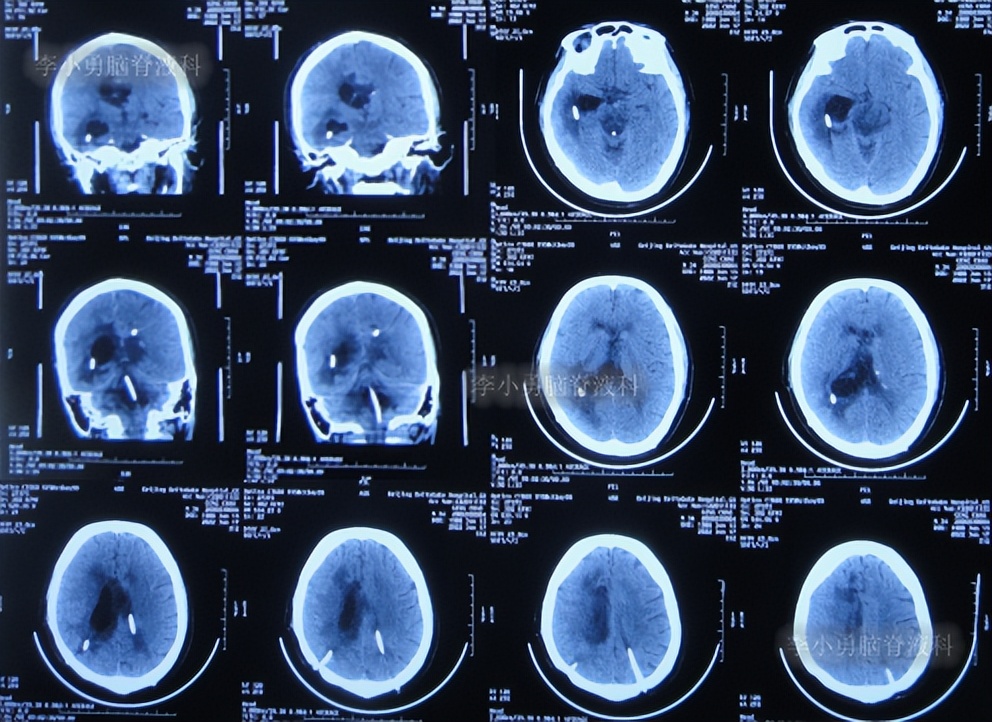

半月后即2022年6月17日,第3次住入李小勇脑脊液科,入院时:进食差,言语混乱,记忆力差,行走差(图-52);查头颅CT示右侧颞角增大,四脑室也稍大(图-53);肺部CT有感染(图-54)。

图-52:2022年6月17 日入院时

图-53:入院时头颅CT

图-54:肺部CT

2022年6月20日(入院后3天),进行了脑室腹壁外引流术,术前术后头颅CT对比(图-55)。

图-55:2022年6月20日术前术后头颅CT

2022年6月23日(入院治疗6天),查头颅CT示脑室周有水肿(图-56)。

图-56:2022年6月23 日头颅CT

2022年10月7日(入院治疗112天),查头颅CT示脑室周水肿消失,脑室变小(图-57)。

图-57:2022年10月7日头颅CT

2022年10月25日(入院治疗130天),肺部 CT示感染有好转(图-58);常规检查头颅CT示脑室引流术后状态,未见异常(图-59),考虑夹闭侧脑室和颞角引流管。

图-58:2022年10月25日头颅CT

图-59:2022年10月25日肺部 CT

夹闭引流管后10天左右,脑室未扩张,于是拔除了侧脑室和颞角的引流管,进行了脑室腹腔分流术。

2022年11月15日(李小勇脑脊液科治疗151天)出院,出院时:意识正常,言语交流基本正常,自己走路差点(图-60);头颅CT示未见异常(图-61)。

图-60:2022年11月15日

图-61:出院时头颅CT